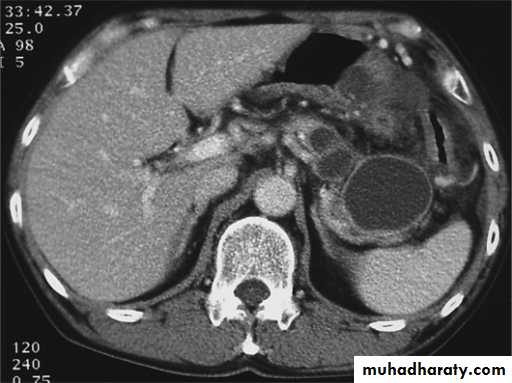

Pancreatitis

Patient present with abdominal pain , vomiting with or without jaundice , increase amylase levelCT finding

Enlargement of the pancreas focal or generalized increase in size .

Hypo density within the pancreas focal or generalized due to the edema .

Peri pancreatic fluid collection & edema around the pancreas .

The fluid around the pancreas if persist more than 6 w become encysted leading to the pancreatic pseudo cyst any area could be affected .

Edema of the wall of the stomach .